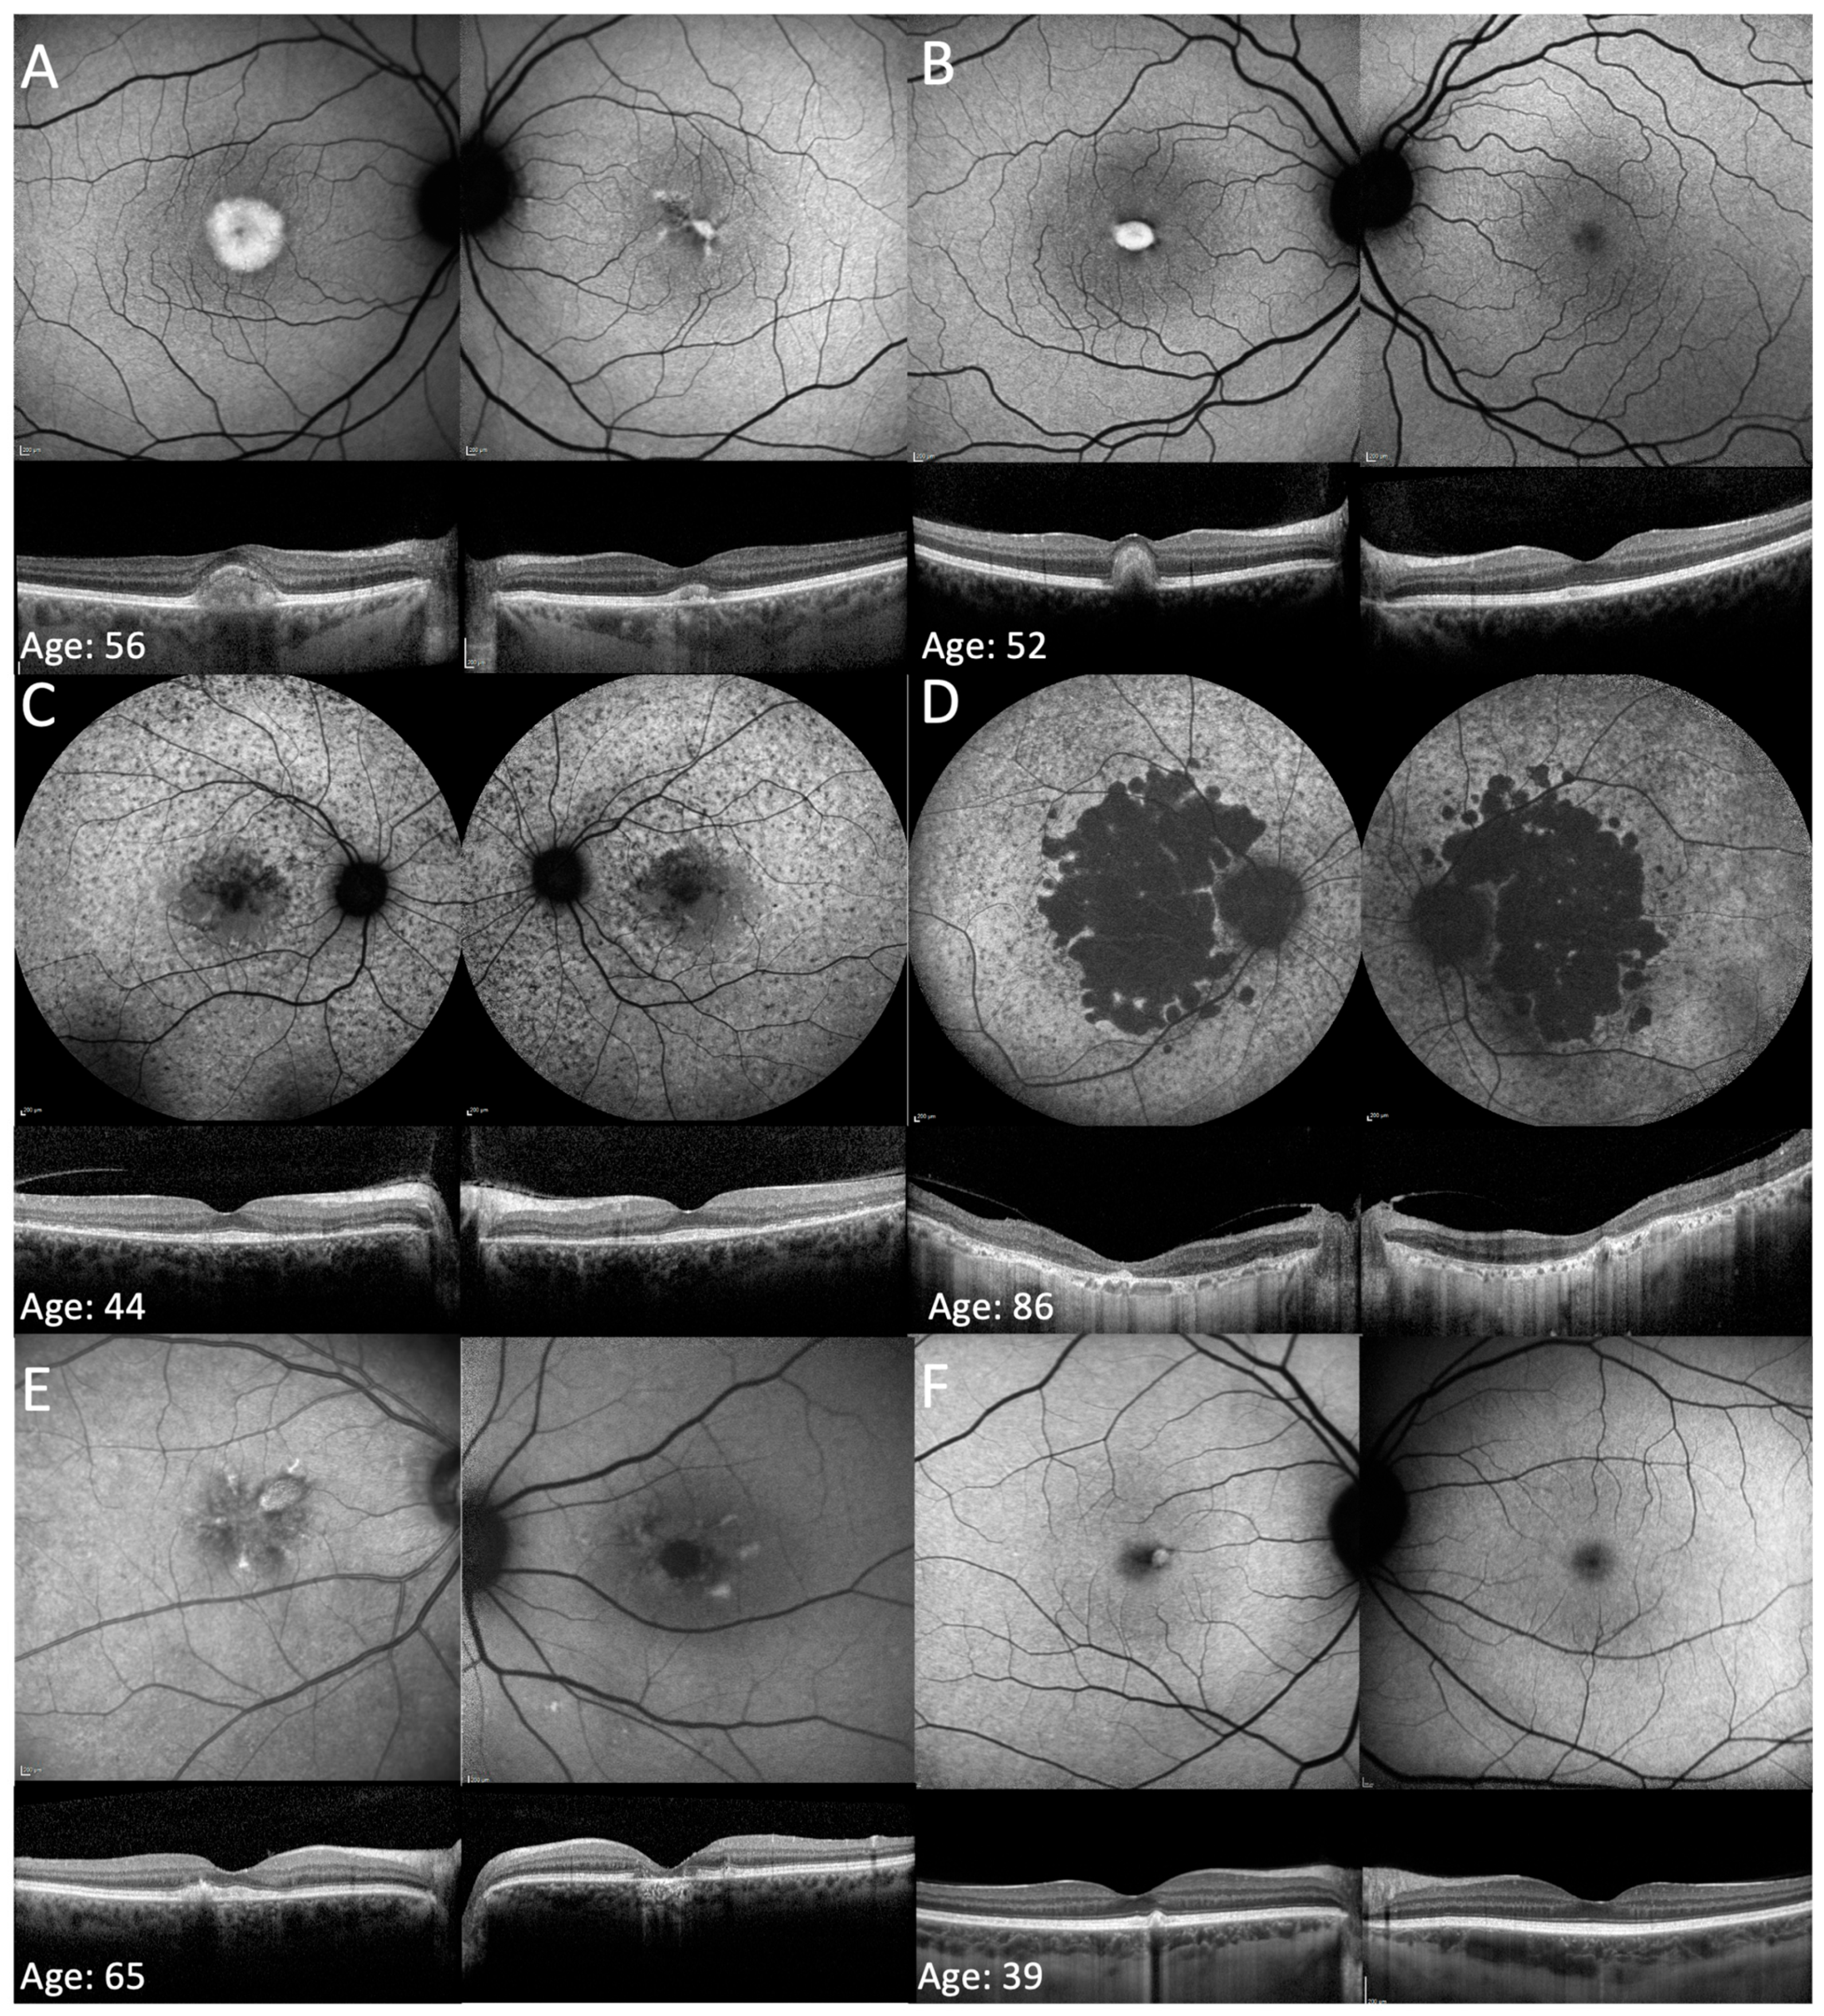

3.2. Phenotype on FAF and OCT Imaging

| 9B | c.469G>A | p.(Asp157Asn) | F | 65 | NR | NR | AD (daughter 9A) | 0.20 | 0.54 | 0.40 | 1.00 | 8 | PD->PSPD | Macular atrophy + flecks |

| 24 | c.272_273insAT | p.(Ala92fs) | F | 69 | 55 | Photophobia and delayed dark adaptation | AD | 0.52 | 0.22 | 1.04 | 0.22 | 7 | PSPD + heterogenous background AF | Macular atrophy |

| 27A | c.612C>G | p.(Tyr204*) | F | 44 | 44 | Delayed dark adaptation, constricted visual fields and photosensitivity | AD (mother 27B) | 0 | 0.1 | 0 | 0.1 | 6 | PSPD + heterogenous background AF | Macular atrophy + foveal sparing |

| 27B | c.612C>G | p.(Tyr204*) | F | 86 | 50 | Blurred vision | AD (daughter 27A) | HM | 1.3 | NA | NA | 0 | PSPD + heterogenous background AF | Macular atrophy |

| 28 | c.629C>G | p.(Pro210Arg) | M | 56 | 54 | Blurred vision and delayed dark adaptation | Sporadic | −0.14 | −0.12 | 1.18 | 0.18 | 11 | PSPD | Flecks + vitelliform lesion |

| 30 | c.394delC | p.(Gln132fs) | F | 63 | 54 | Distortion, delayed dark adaptation, photosensitivity, and central scotoma | AD | 0.08 | 0.1 | 0.64 | 0.28 | 9 | PSPD | Macular atrophy + foveal sparing OS |